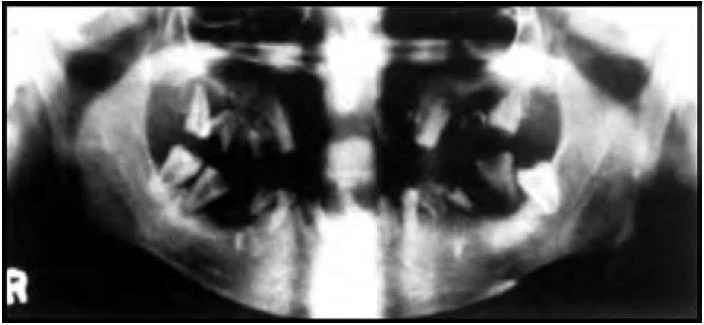

Bộ răng vĩnh viễn hình thành bên trong xương hàm sớm sau khi sinh. Quá trình canxi hoá bắt đầu lúc sinh với việc canxi hoá các múi của răng cối lớn vĩnh viễn thứ nhất và tiếp tục cho đến năm 25 tuổi. Hoàn thành canxi hoá thân răng cửa xảy ra ở tuổi thứ 4 đến 5 và của các răng vĩnh viễn khác ở tuổi thứ 6 đến 8 ngoại trừ răng cối lớn thứ ba. Vì vậy tổng thời kỳ canxi hoá răng là khoảng 10 năm. Các răng cửa vĩnh viễn phát triển về phía trong các răng cửa sữa và di chuyển về phía môi khi mọc lên. Răng cố nhỏ phát triển bên dưới vùng phân kỳ của các chân răng cối sữa.

Nolla (1960) đã đưa ra các giai đoạn phát triển răng từ phim panorex. Khoảng vào độ tuổi 13, tất cả các răng vĩnh viễn ngoại trừ răng cối lớn thứ ba sẽ mọc hoàn toàn trong miệng. Trước khi răng cửa sữa rụng, có 48 răng/bộ phận răng hiện diện trong xương hàm.